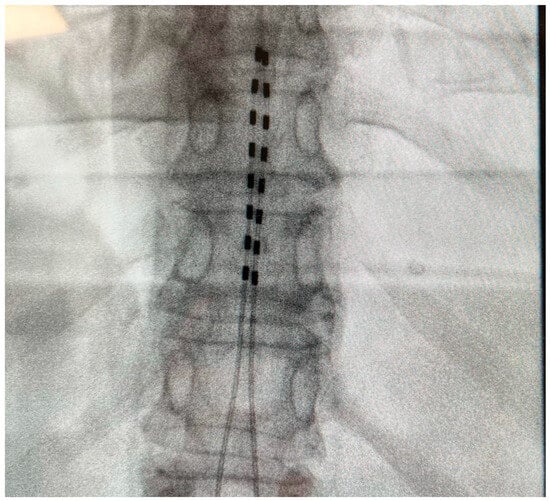

Patients were implanted with epidural percutaneous leads targeting the lower extremities (T10–T11), and upper extremities (C4–C7) if necessary, and with an implantable pulse generator (IPG) system (Alpha WaveWriterTM, Boston Scientific Corporation, Valencia, CA, USA) (Figure 1). The implantation procedure and criteria for permanent implants were based on established standards and were performed in accordance with the center’s standard practice (pain relief ≥ 50% based on a trial phase).

Figure 1.

Typical lead placement.